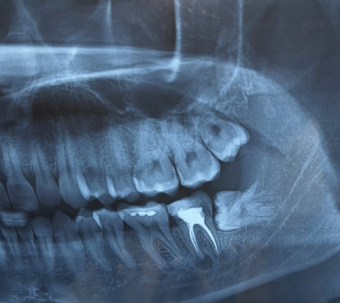

Extractiile molarilor de minte inclusi sau semi-inclusi pot deveni un adevarat test atat pentru pacienti, cat si pentru medicii stomatologi. Acesti molari ocupa o pozitie delicata in unghiul mandibulei, un os de o duritate extrema, si se afla in imediata apropiere a unui element anatomic crucial – nervul alveolar inferior. Acest nerv inerveaza jumatate din fata, iar orice leziune accidentala poate conduce la anestezie, adica lipsa de sensibilitate in aceasta zona. De aceea, extractia acestor molari trebuie efectuata doar de medici cu experienta in chirurgie stomatologica.

Pentru a ilustra importanta experientei medicului stomatolog, va prezentam cazul lui Calin, un tanar de 23 de ani, care s-a confruntat cu un molar de minte inclus si orizontalizat. Starea sa de stres inainte de interventie a fost considerabila. Cu toate acestea, dupa administrarea unei anestezii locale, extractia s-a desfasurat excelent, intr-un timp de aproximativ 10 minute. Calin a parasit cabinetul fericit si linistit. Dupa cateva ore de la extractie, acesta a mentionat ca se simte foarte bine, avand in vedere ca a luat o pastila impotriva durerii.